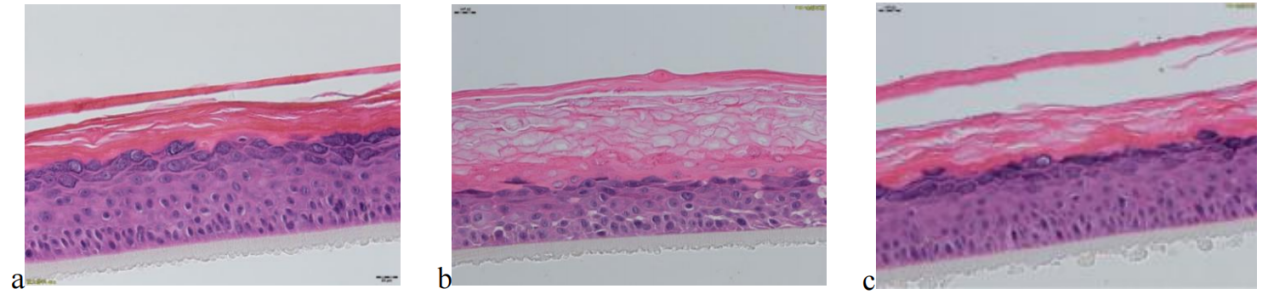

待測活性物與BAP聯(lián)合作用于EpiKutis® 皮膚模型后,形態(tài)學(xué)結(jié)果見圖6。與空白對照組(Control)相比,刺激組(BAP)的角質(zhì)層增厚、排列疏松、空泡明顯且分化不完全;活細胞層(顆粒層、棘層、基底層)活細胞數(shù)目減少,基底層細胞空泡明顯,排列疏散。

圖 6 不同處理條件下表皮模型的形態(tài)學(xué)變化情況(放大40倍)

(a.空白對照組,b.BAP刺激組,c.待測活性物組)